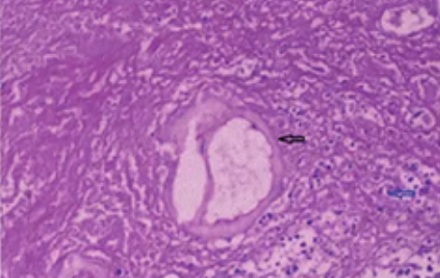

包虫的成虫生活在狗的肠道里,在 30 厘米长的狗小肠内,成虫的寄生数量可高达 3 万余条,每日可排出约 10 万个虫卵。——数据来源:《甘孜日报》

人在接触狗后不洗手就吃东西,就可能误食虫卵,感染包虫病。